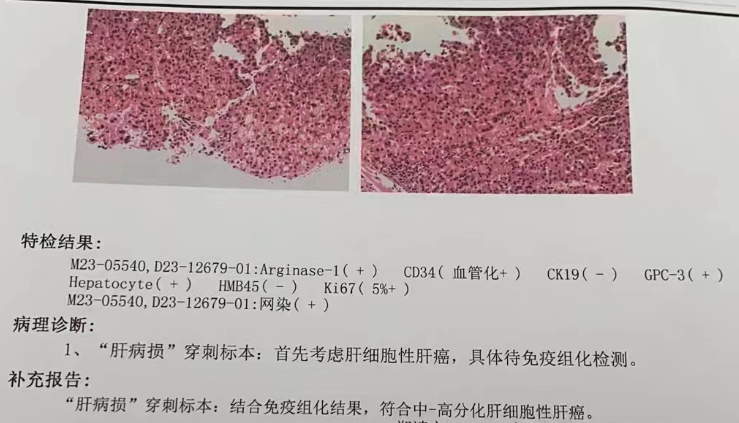

▲ 术后病理结果